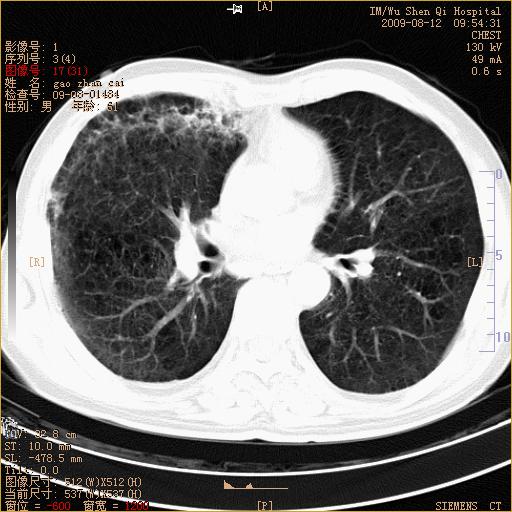

1、右上肺继发性肺结核合并感染;2、肺气肿。

右肺间质纤维化右肺间质性肺炎

右肺弥漫性间质性改变

右上肺干酪性肺炎,肺气肿

右肺间质性肺炎,肺气肿

考虑右肺结核, 右肺间质性改变,肺气肿。

1)右肺上叶感染性病变;建议抗炎治疗后复查。2)肺气肿。

右肺上叶支扩并感染,肺间质纤维化,肺气肿,右肺门淋巴结肿大。建议抗炎治疗后复查。